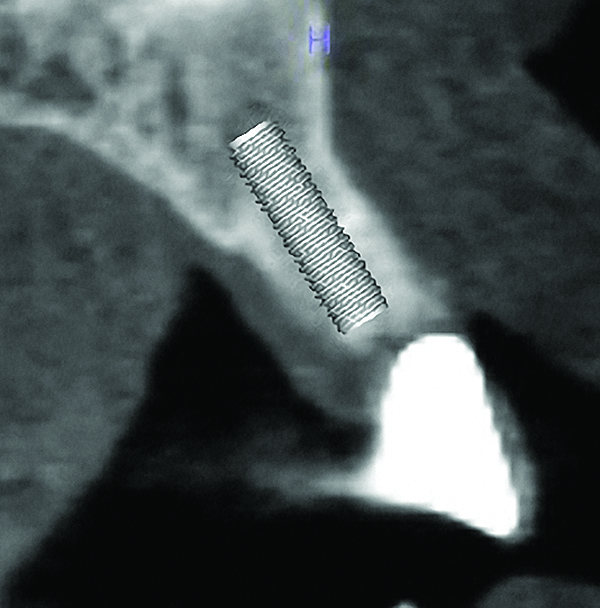

Fig 9. Radiograph taken at the time of implant placement confirming that the implant is precisely positioned, matching the presurgical plan.

Figure 9

A number of things can be done to improve guide stability and eliminate guide movement during guided surgery. Cassetta et al recommended adequate flap elevation so as not to impinge upon the guide, to thus eliminate flap tension as a cause for guide instability.11 This requires sufficient and often extensive flap reflection. Additionally, they recommended guide fixation using horizontally placed bone fixation pins. The pins should be arranged at least as a tripod for maximum guide stability during surgery. In these cases horizontal osteotomies are planned presurgically during the digital planning, and at the time of surgery they are prepared through the mucosa into the underlying alveolar bone, through which the fixation pins are placed. It is important to pay close attention in planning and later placing horizontal fixation pins so as to avoid vital structures such as adjacent tooth roots and neurovascular canals. In dentate and partially dentate patients, the surgeon can place a thin layer of flowable material such as bite registration material on the inner surface of the guide, then immediately seat the guide in proper position. Figure 7 through Figure 9 demonstrate this technique; the guide is secured in proper position, assuring its stability and accurately creating an osteotomy.